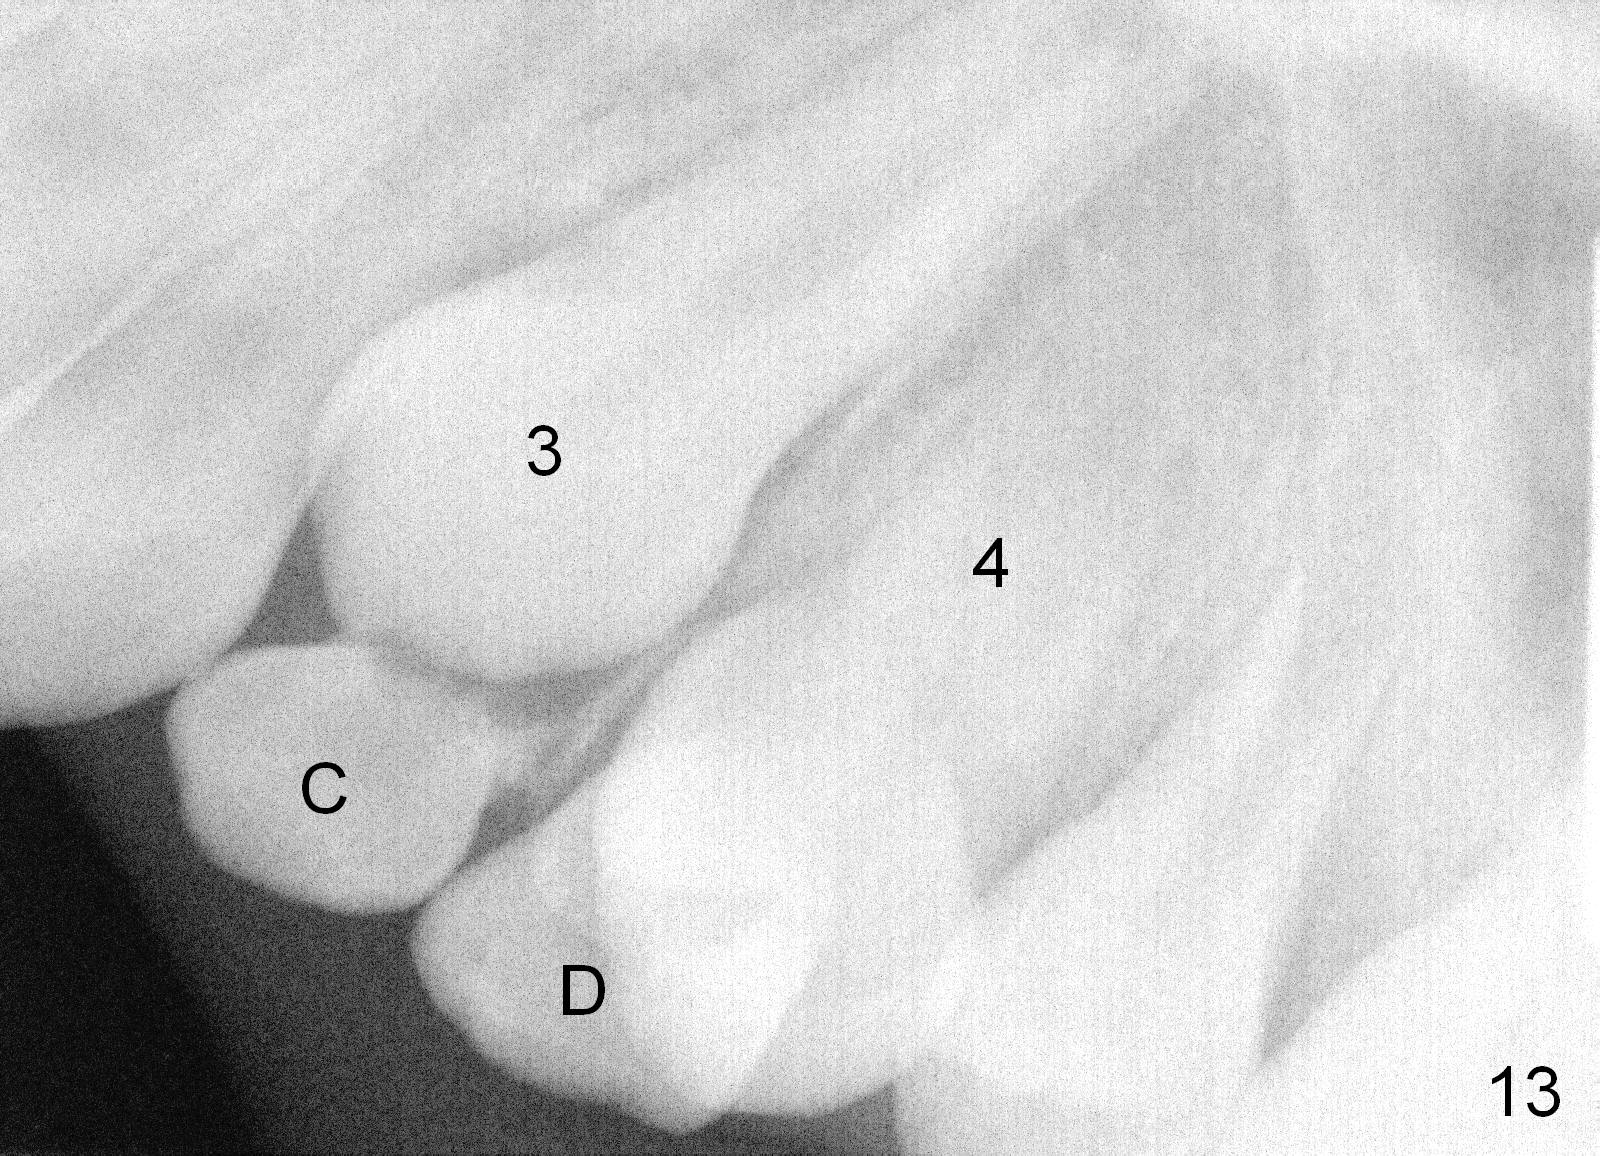

A 11-year-old boy has history of asthma. His father has sleep apnea with similar Class II malocclusion. Pan was taken for the boy 3 years ago (Fig.1). His mother wants to have orthodontic treatment as early as possible, because of protrusive upper anterior teeth. The dentition is permanent except the upper left canine and 1st molar (Fig.7,10,12,13 C, D). It appears that there is bilateral Class II occlusion at canine by half a tooth (Fig.9-12). The malocclusion and facial profile can be easily corrected with extraction of the upper 1st bicuspids.